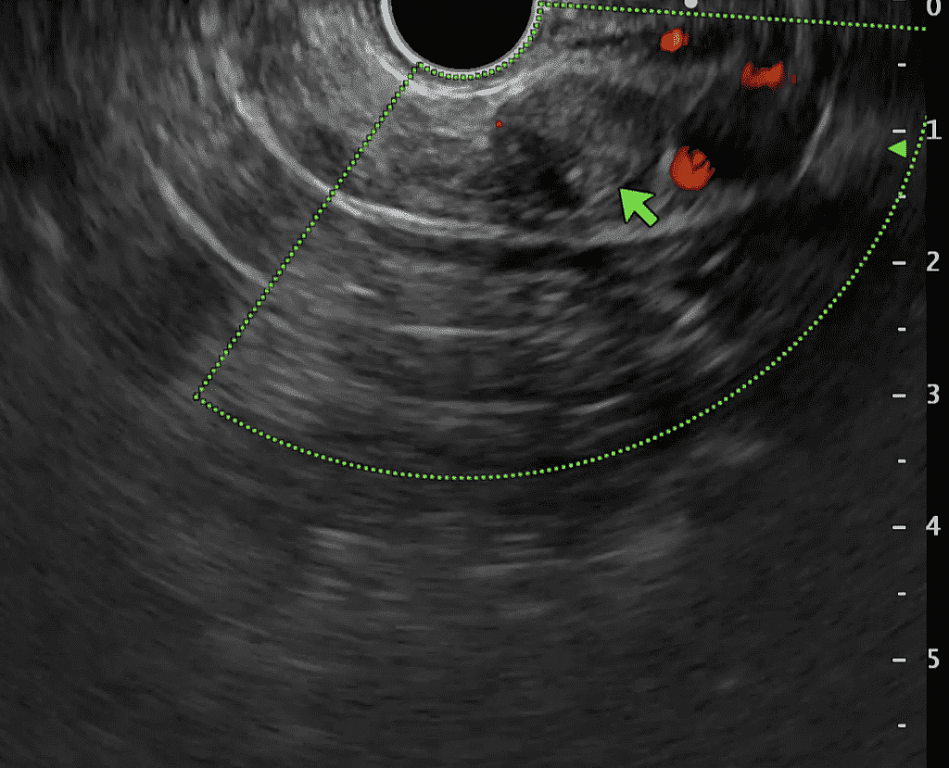

Выполнение КТ или МРТ с контрастированием помогает выявить инсулиному в поджелудочной железе и точно определить ее местоположение. Однако, в некоторых случаях обнаружение инсулиномы на КТ или МРТ может быть затруднительным. Тогда используется эндоультрасонография или эндоскопическое УЗИ.